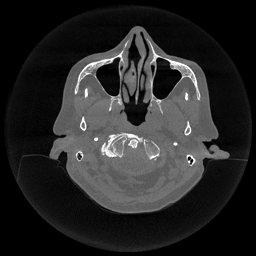

III-D Real Clinical Data Experiment

The experimental results on clinical head data are shown in Fig. 4. The reference images were reconstructed using the fast iterative shrinkage-thresholding algorithm (FISTA) with total variation regularization from non-truncated projection data. In the WCE reconstructions (Fig. 4(b)), severe truncation prevents accurate recovery of anatomical structures outside the FOV. Despite being trained solely on simulated data with a domain gap, all deep learning models can restore a substantial portion of the missing anatomy. Among them, the diffusion-based methods recover soft-tissue boundaries more faithfully than the conventional deep learning approach FBPConvNet, highlighting their stronger image generation capability. However, cDDPM reconstructions exhibit more noticeable noise than those from other methods, consistent with the simulated data results. The patchDiffusion model introduces artifacts within the FOV, likely due to its patch-wise processing strategy. While I2SB shares the same limitations as other diffusion models in perfectly restoring soft-tissue detail, it produces fewer residual noise patterns and fewer artifacts within the FOV boundaries. Overall, Fig. 4 demonstrates the strong efficacy of I2SB in reconstructing real CBCT data.